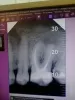

В среду разболелся зуб, нижняя шестерка справа. В четверг обратилась к стоматологу, сделали снимок. На снимке увидели кисту. Врач прописал антибиотик Амоксициллин 500, три раза в день. Принимаю с вечера четверга. С вечера пятницы боль усилилась. Боль стала отдавать в верхние зубы и правое ухо, болит также правая часть языка. Боль то усиливается, то просто ноет. Зуб был вылечен 15 лет назад у платного стоматолога.

Прикрепленые фото

В области дистального корня имеется разряжение костной ткани, вероятнее всего это киста. Необходимо купировать процесс. В идеале, диагноз киста, в настоящее время не ставят, и рекомендуется попытаться перелечить зуб и понаблюдать в динамике, но гарантировать положительную динамику при таких объемах разряжения очень не просто.